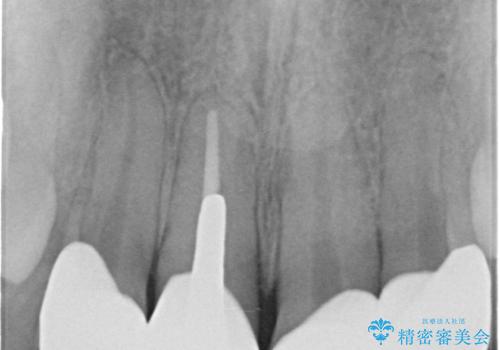

- 前歯のクラウンの見た目が不自然、歯の根元が見えたり金属色が気になるので改善したい、とセラミック治療を希望され来院されました。

歯肉の位置変化による審美障害を改善するため、オールセラミックジルコニアクラウンで再治療を行い審美性の改善を計画します。